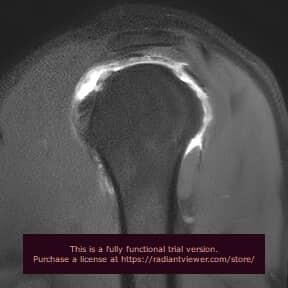

Hace unos años, un joven deportista de élite llegó a nuestro servicio de radiología con una historia frustrante. Llevaba meses con dolor en el hombro que le impedía lanzar, había pasado por resonancias magnéticas convencionales que mostraban "todo normal", y los médicos empezaban a dudar de si el problema era real. Cuando finalmente se realizó una resonancia magnética artrografía, la imagen fue clarificadora: una lesión tipo SLAP (desgarro del labrum superior) que la RM estándar no había podido caracterizar con precisión.

Hombro: El territorio de la artro-RM por excelencia

En el hombro, la artrografia por RM es el estándar de referencia para:

- Lesiones del labrum glenoideo: especialmente lesiones de Bankart (post-luxación) y lesiones tipo SLAP (superiores, en deportistas de lanzamiento)

- Ligamentos gleno-humerales: evaluación de inestabilidad crónica

- Inserción del tendón de la porción larga del bíceps: para detectar desinserciones o patología del ancla bicipital

La sensibilidad alcanza el 92% para lesiones de Bankart y el 82-98% para lesiones SLAP, cifras que la RM convencional no puede igualar.